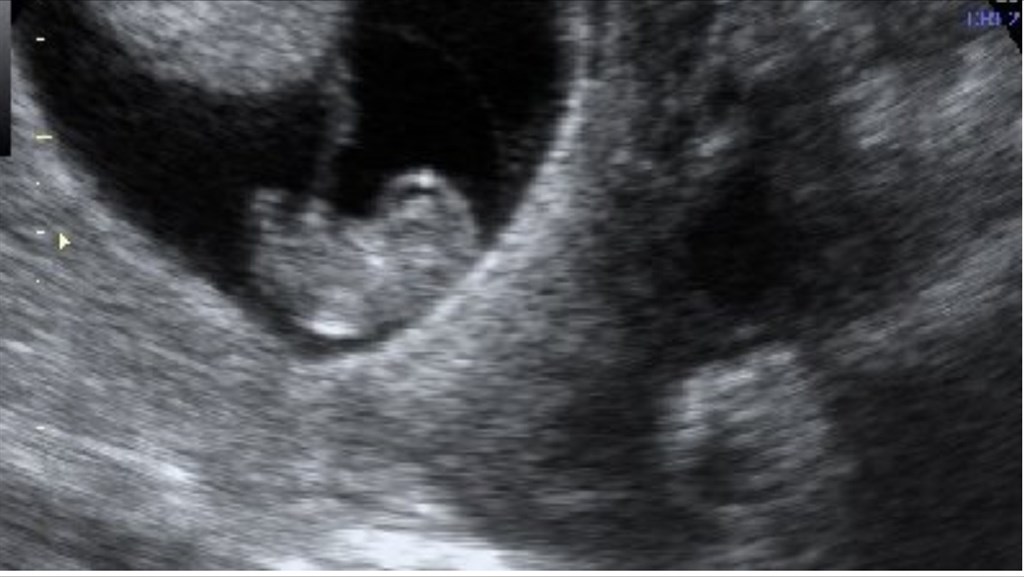

Det skulle have været lillebror eller lillesøster, hvorfor skulle det ende sådan

Vi sidder så lige og snakker om billedet, og kan ikke finde ud af hvor langt henne jeg har været, vi syntes begge den er stor, hvad ser i ????